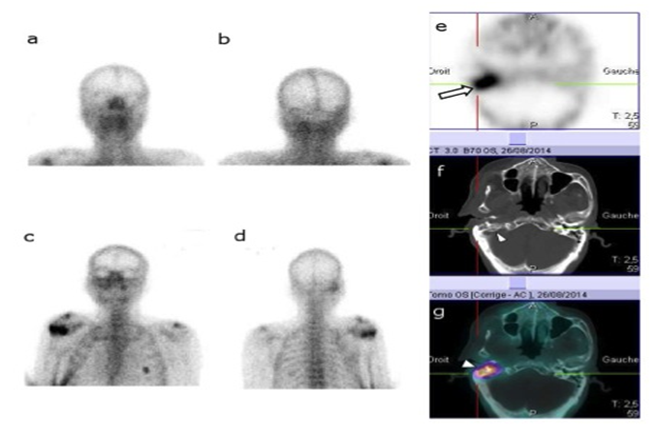

Figure 3, A 76year old diabetic male, presented with severe otalgia and facial nerve palsy. The clinical exam showed inflammation and stenosis of the external auditory canal. Blood pool images (a, b) were normal. Delayed static images (c, d) showed slight increased uptake in the temporal bone region. Planar BS was judged to be negative. SPECT image (e) showed obvious increased radiotracer uptake in the petrous portion of the right temporal bone (arrow). CT image (f) showed right petrous bone osteolysis (arrowhead). SPECT/CT Image (g) showed increased radiotracer uptake in petrous (arrowhead) and mastoid portion of right temporal bone. Considering clinical follow and imaging findings, the final diagnosis was NOE. This case illustrate that SPECT and SPECT/CT are more sensitive than Planar BS.

Figure 3 The clinical exam showed inflammation and stenosis of the external auditory canal.